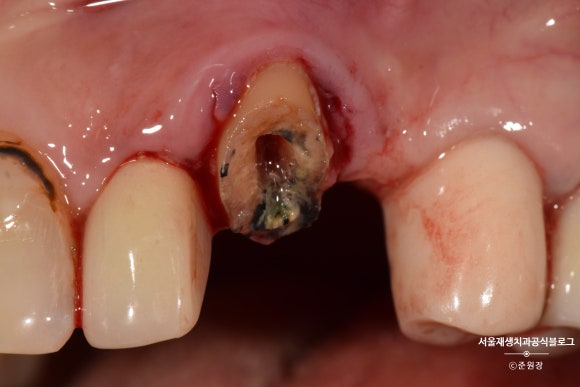

깊은 충치로 머리가 간신히 남은 치아입니다.

머리도 얼마 안남았는데...

크라운을 씌우기 불안할 만큼 잔존치질이 부족합니다.

이 경우 가장 흔하게 선택하는 정답지는,

발치 후 임플란트겠지요.